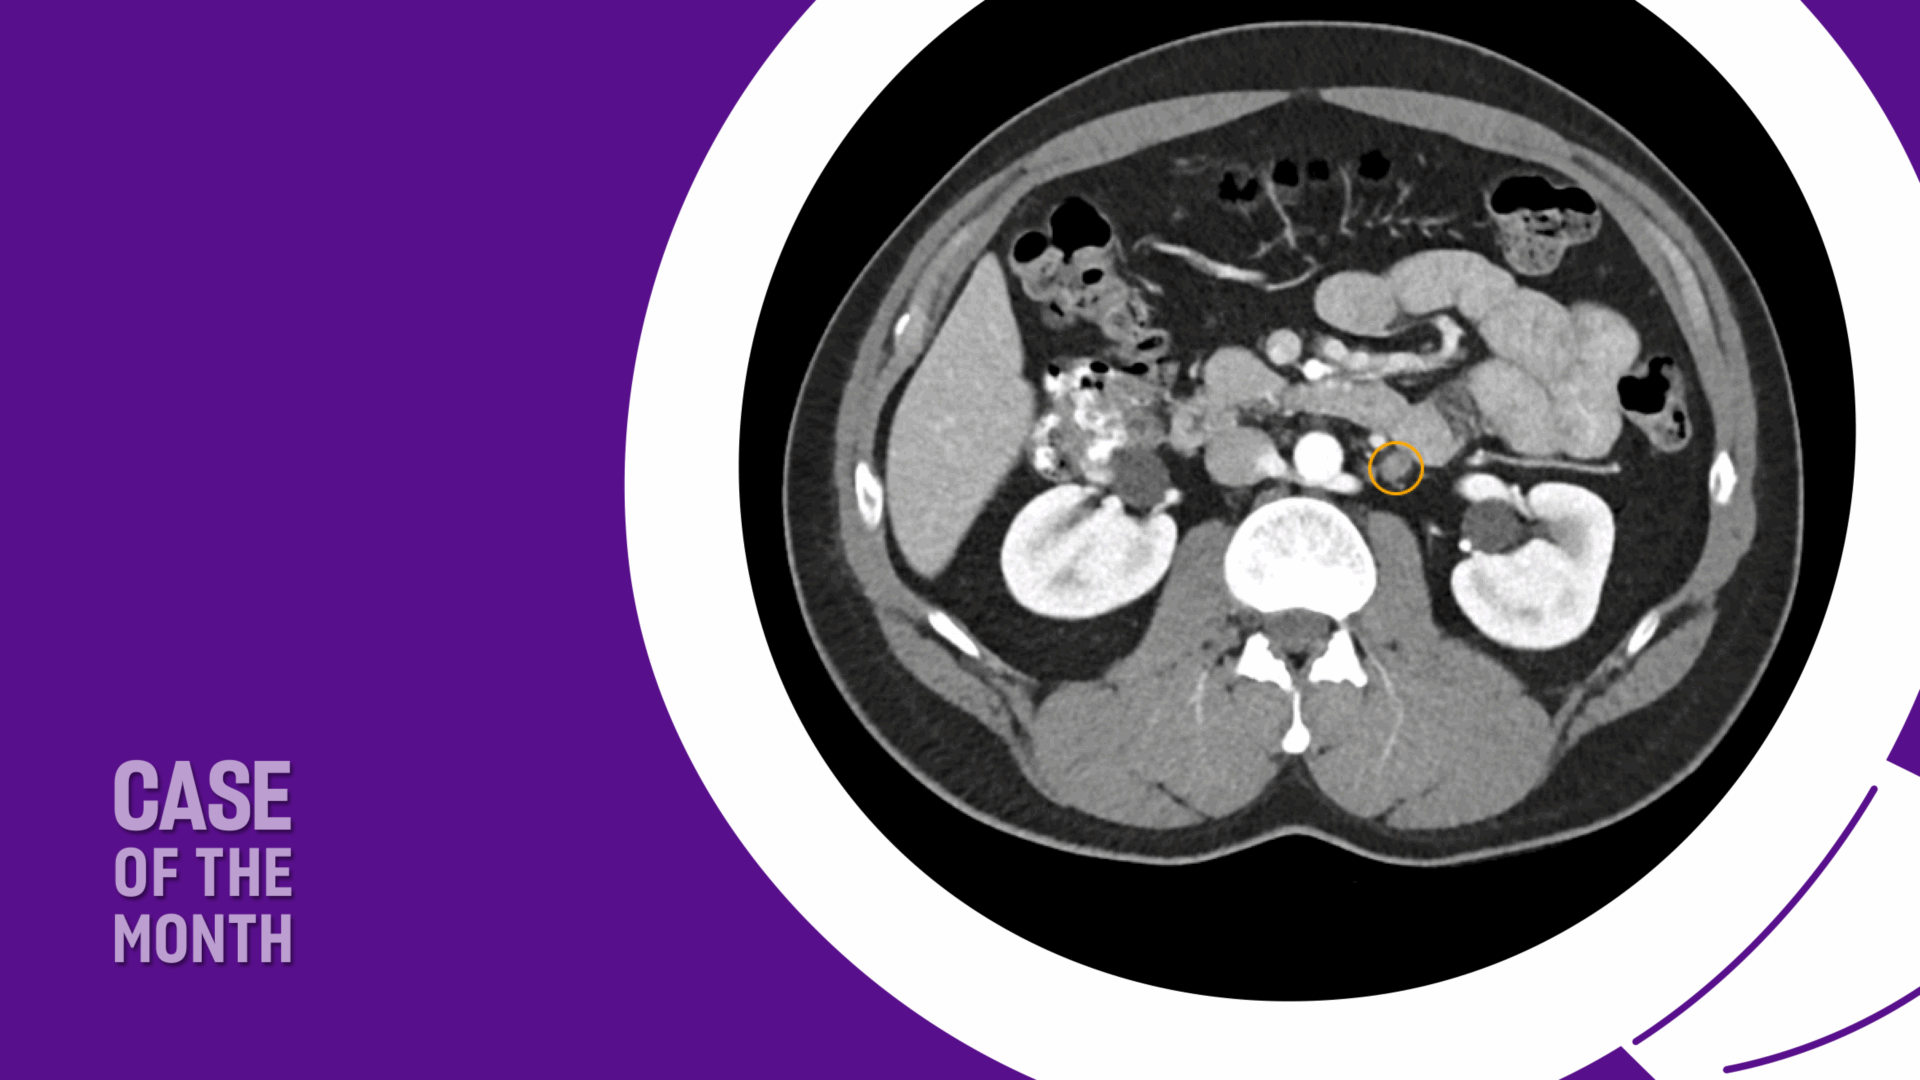

The patient was appropriately managed with active surveillance. Six months following orchiectomy, surveillance CT imaging demonstrated two enlarged para-aortic lymph nodes measuring 1.5 cm, consistent with metastatic disease (Figure 1). CT of the chest remained negative, and serum tumor markers continued to be within normal range.